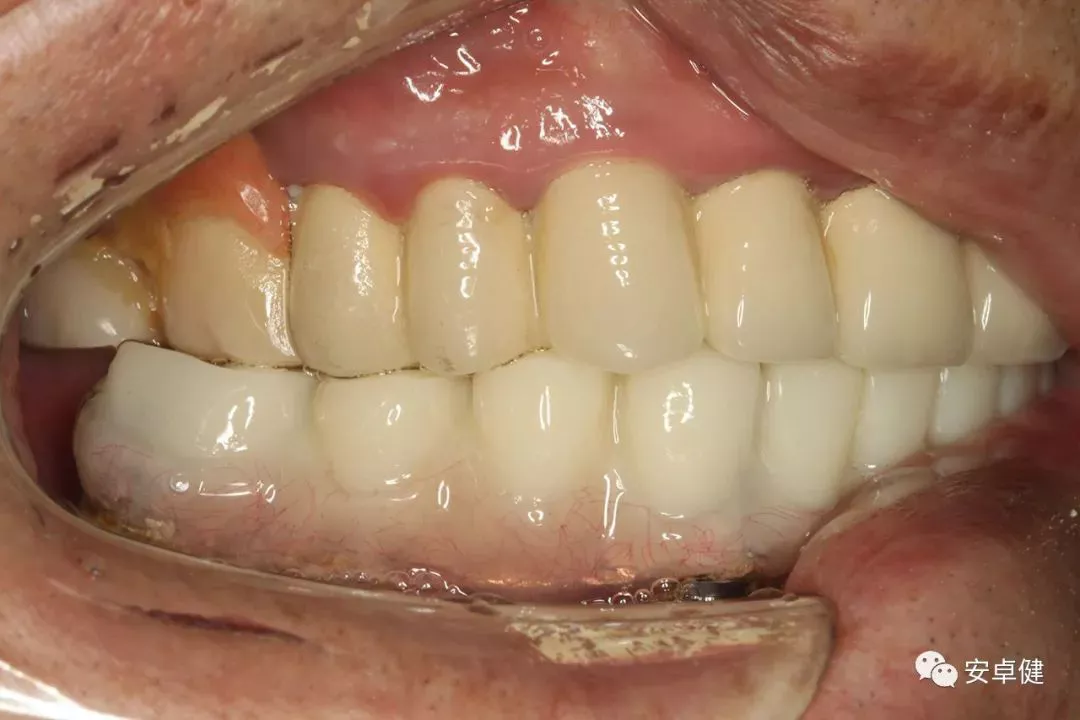

戴牙后4个月复诊正面咬合照

戴牙后4个月复诊正面微张照

戴牙后4个月复诊合面照

• 修复体外形能够正确恢复面下1/3高度及侧貌;

• 患者可获得较为稳定的咬合关系,并满足其咀嚼功能的需求;

• 患者42、46部位牙龈退缩,缺乏足够的角化龈,为方便后期清洁维护,选择穿龈较高的龈上肩台;

• 口内观察,修复体边缘金属基台颜色暴露,但由于其处于下颌后牙非微笑暴露区,故对临床整体美观效果的影响在患者可接受范围内。

• 随访可见患者口腔卫生状况可,牙龈无红肿;

• 下颌修复体状态良好,无修复体机械并发症;

• 种植体基台稳定性良好,无松动;

• 种植体无松动,周围无红肿、溢脓及疼痛表现;

• 正中、前伸及侧方咬合检查可见咬合印记分布均匀,咬合关系良好;

• 患者反映日常使用良好,舒适性佳,满意度高。